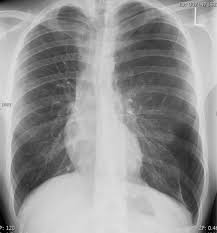

In this video, you'll learn how to identify when radiological pleura is abnormal and the key signs to look out for when trying to diagnose a pneumothorax. Check spelling or type a new query. When pneumothorax with its accompanying emphysema occurs as a complication of bronchoscopy, symptoms are usually severe, and require treatment. When a pneumothorax is clinically suspected, we routinely perform cxr on both inspiration (as per usual) and expiration. Agus suharto basuki, sp.p fakultas kedokteranuniversitas muhammadiyah surakarta 2011 2. Scarcely less important is the selection of the positionmost favorable for obtaining information in fluoroscopicand Special attention is paid to tension pneumothorax, to. A pneumothorax, légmell (ptx), az az életveszélyes akut kórállapot, amikor a mellhártya zsigeri és fali lemeze közé, azaz a mellhártyaüregbe levegő jut kívülről (a mellkasfal sérülésén át) vagy belülről (a tüdő vagy oesophagus folytonosságmegszakadása útján).

On an expiratory film, a pneumothorax will appear relatively larger, taking up a larger percentage of the thoracic cavity.

The typical effects of a fibrothorax are shown: The incidence is approximately 10 out of 100 000 residents per year. Therefore, it is mandatory to treat it safely. In this video, you'll learn how to identify when radiological pleura is abnormal and the key signs to look out for when trying to diagnose a pneumothorax. On an expiratory film, a pneumothorax will appear relatively larger, taking up a larger percentage of the thoracic cavity.

It entails few complications and little risk. Primärer spontanpneumothorax, es besteht keine gesicherte ursache und die betroffene person ist gesund. Check spelling or type a new query. Tillståndet uppstår ofta spontant hos unga och friska utan känd lungsjukdom, men kan drabba alla åldrar med eller utan tydlig orsak An occult pneumothorax refers to one missed on initial imaging, usually a supine /semierect chest radiograph 24. It occurs through an immediate disruption of the visceral pleura that results in an accumulation of air in the pleural space. Chest (1977), 71, 211 bilateral spontaneous pneumothorax with pulmonary metastases from synovial cell sarcoma harjit singh, nachhattar singh and ravinderpal kaur government medical college and rajindra hospital, patiala, punjab, india summary the association of bilateral spontaneous pneumothorax with pulmonary metastases is rare. Temaet er også relevant for andre helsefagutdanninger.

An occult pneumothorax refers to one missed on initial imaging, usually a supine /semierect chest radiograph 24. Agus suharto basuki, sp.p fakultas kedokteranuniversitas muhammadiyah surakarta 2011 2. Traumatischer pneumothorax, die ursache ist ein trauma. Maybe you would like to learn more about one of these? The pleura is pushed further away from the chest wall, and the pneumothorax is usually a lot … Louis duringthepast fewyears, therehave been many importantadvances in the diagnostic method of thoracic conditions. Pneumothorax kan være spontan, traumatisk eller iatrogen. Therefore, it is mandatory to treat it safely. Disponerende faktorer er rygning (inkl. Sekundärer spontanpneumothorax, wird durch lungenerkrankungen oder krankheiten anderer organe verursacht. The typical effects of a fibrothorax are shown: On all expiratory chest roentgenograms the pneumothorax was seen, of the 54 inspiratory ones two investigators missed one very small apical pneumothorax. It occurs through an immediate disruption of the visceral pleura that results in an accumulation of air in the pleural space.

Of air is practically undetectable by physical examination, and one containing from 200 to 250 cc. Pneumo, luft, och thorax, bröstkorg) är ett tillstånd då ena eller båda lungorna komprimeras till följd av luftansamling i lungsäcken. When a pneumothorax is clinically suspected, we routinely perform cxr on both inspiration (as per usual) and expiration. In this video, you'll learn how to identify when radiological pleura is abnormal and the key signs to look out for when trying to diagnose a pneumothorax. On an expiratory film, a pneumothorax will appear relatively larger, taking up a larger percentage of the thoracic cavity. Louis duringthepast fewyears, therehave been many importantadvances in the diagnostic method of thoracic conditions. Scarcely less important is the selection of the positionmost favorable for obtaining information in fluoroscopicand Tillståndet uppstår ofta spontant hos unga och friska utan känd lungsjukdom, men kan drabba alla åldrar med eller utan tydlig orsak